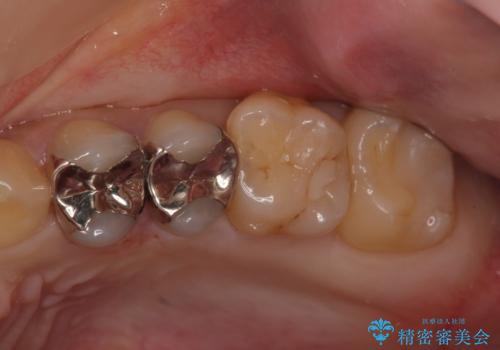

銀歯のやり替え セラミックで白い歯に

口腔内をメタルフリーにしたい

銀の詰め物を白い物にしたい